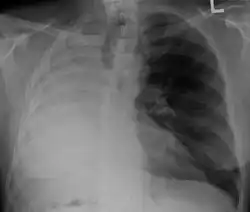

| Left tension pneumothorax with a large, well-demarcated area devoid of lung markings with tracheal deviation and movement of the heart away from the affected side. |

Tension pneumothorax

Tension pneumothorax is an emergent condition in which air gets trapped in the space between the chest wall and the lung. This space is referred to as the pleural space. Because air can't escape from this space, the air pocket grows larger and larger, resulting in the lung collapse closest to the pneumothorax. Forces are transmitted to the mediastinum and effectively "push" the mediastinal structures to the opposite side of the chest.[5]